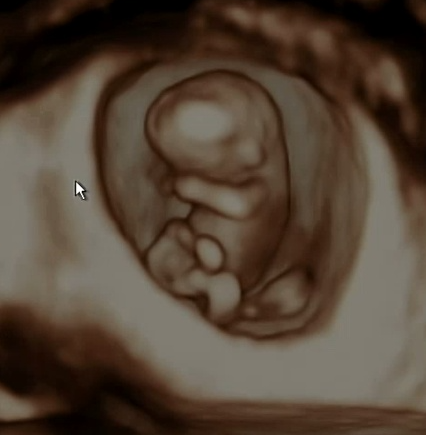

처음 임신을 알게된건 임신 극초기때였습니다. 계속 기다리던 아기라 계속 테스트기를 하기도 했고 느낌이 이상해 산부인과를 방문했지만 초음파로는 보이지 않았고 피검사로 임신을 했다는 사실을 알게됐습니다. 5주가 됐을무렵 아기집이 생기고 난황이 보였습니다.